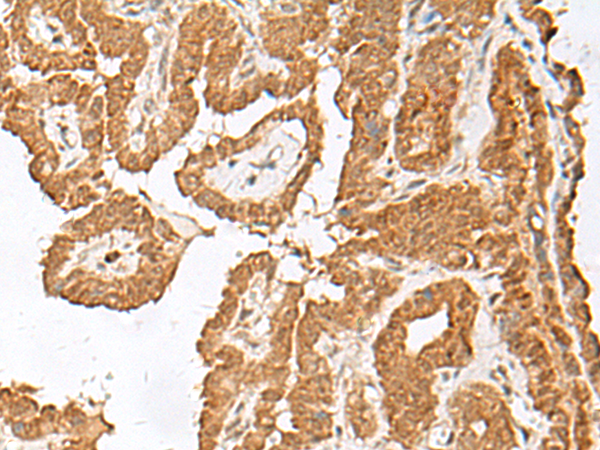

ELISA, IHC |

IHC positive control: |

Human esophagus cancer and Human thyroid cancer |

IHC Recommend dilution: |

40-200 |